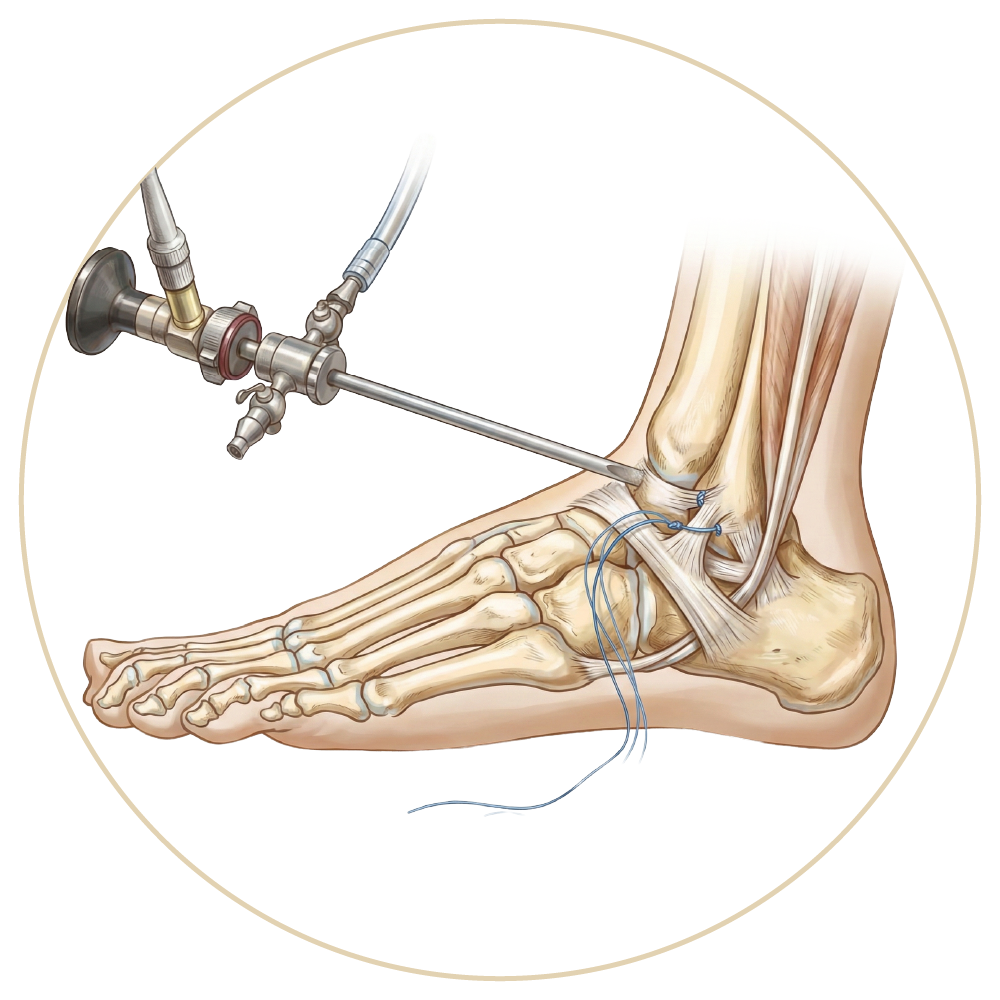

Ayak Bileği Yaralanmaları

Ayak Bileği Protezi

Ayak Bileği Artroskopisi